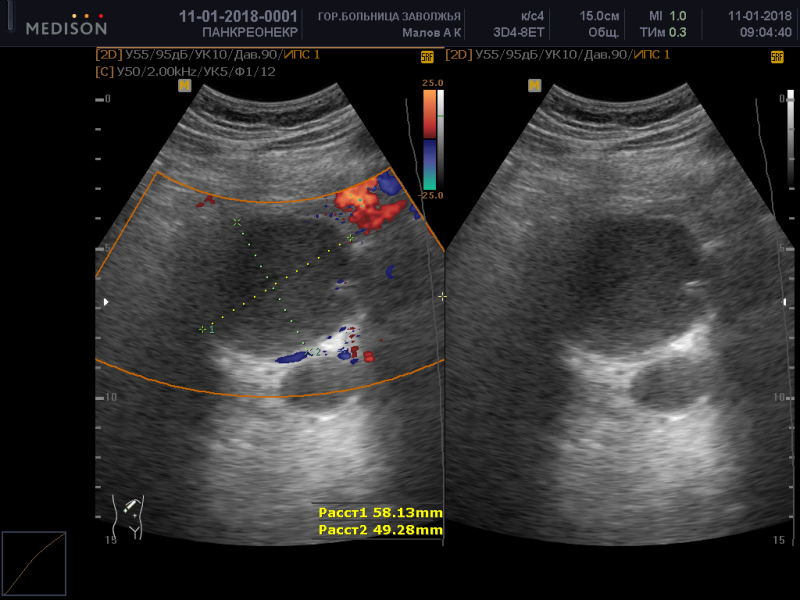

Локализация эхинококковой кисты в поджелудочной железе (с комментарием)

Локализация эхинококковых кист в поджелудочной железе относится к редким формам заболевания и встречается у 0,1—0,21% больных [1, 2]. Как правило, при такой локализации паразитарные кисты одновременно выявляют в других органах — печени, легких, селезенке и пр. [2].

В нашей клинике находился на лечении больной, у которого была выявлена киста только в поджелудочной железе. Приводим это наблюдение.

Больной Э., 41 года, госпитализирован в отделение хирургии № 1 Республиканской больницы № 2 Махачкалы 11.03.14 с жалобами на схваткообразные боли в животе, вздутие живота, тошноту, рвоту. В 2002 г. перенес холецистэктомию.

УЗИ: печень увеличена на 3 см за счет левой доли, структура диффузно неоднородная; диаметр общего желчного протока 7 мм; селезенка не увеличена, диаметр селезеночной вены 10 мм; кистозные образования в брюшной полости и забрюшинном пространстве не выявлены.

18.03 больной оперирован по поводу кисты брюшной полости. В области хвоста поджелудочной железы выявлено округое плотное опухолевидное образование размером 4×4 см, спаянное с селезеночными артерией и веной.

Результаты морфологического исследования: эхинококковая киста с участками обызвествления хитиновой оболочки.

Заключительный диагноз: эхинококковая киста поджелудочной железы, брюшинные спайки.

В этом наблюдении представляет интерес не только редкая локализация эхинококковой кисты, но и отсутствие паразитарных кист в других органах (печени, легких).

Представлен редкий случай локализации эхинококковой кисты в поджелудочной железе.

При таком варианте расположения эхинококковой кисты показан органосохраняющий вариант операции — дистальная резекция поджелудочной железы с сохранением селезенки (в специализированной клинике — срединная резекция поджелудочной железы). Оптимальным явился бы лапароскопический способ выполнения операции. Независимо от объема и способа выполнения операции следовало соблюдать эпидемические профилактические меры (аспирация содержимого кисты с последующим введением в ее просвет гипертонического раствора хлористого натрия и обкладывание операционного поля салфетками с тем же раствором. Утверждение авторов о том, что у больного единственная эхинококковая киста требует дополнительного исследования — КТ или МРТ с прицельным изучением печени. Выполненное перед операцией УЗИ, при котором не была диагностирована киста поджелудочной железы, не может служить критерием для исключения эхинококкового поражения печени.